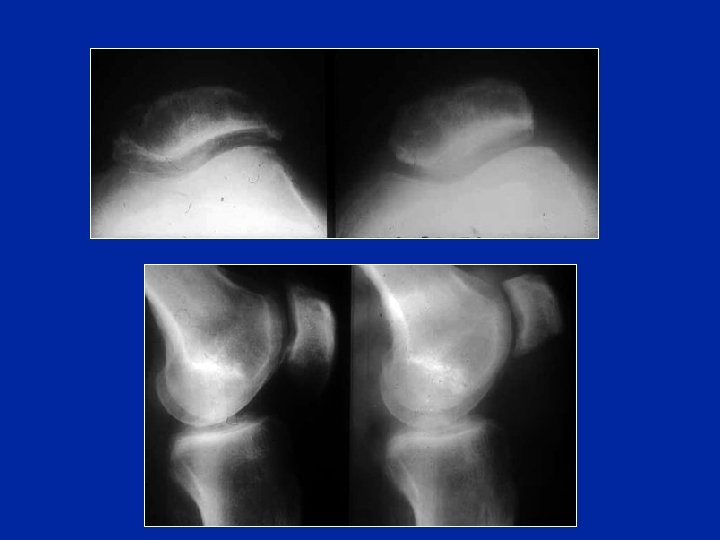

Diagnostic différentiel Patella bipartita ou tripartita Anomalies congénitales souvent bilatérales (pouvant devenir symptômatiques après un traumatisme)

Patella bipartita Parfois douloureuses et conduisant à des opérations de régularisation